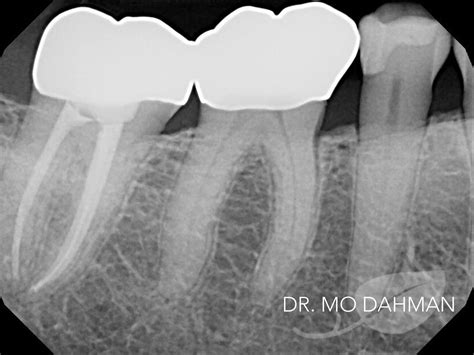

Crown X Ray Dental technology works by using a combination of X-rays and computer technology to create detailed images of the teeth and surrounding structures. The process involves several steps:

• Image Capture: The patient is positioned in the imaging machine, which rotates around the head to capture images from multiple angles.

• Data Processing: The captured images are sent to a computer, where specialized software processes the data to create a three-dimensional model.

• Image Analysis: Dentists can then analyze the 3D model to identify any issues or abnormalities.

This process is typically completed in a matter of minutes, making it a convenient option for both patients and dental professionals.